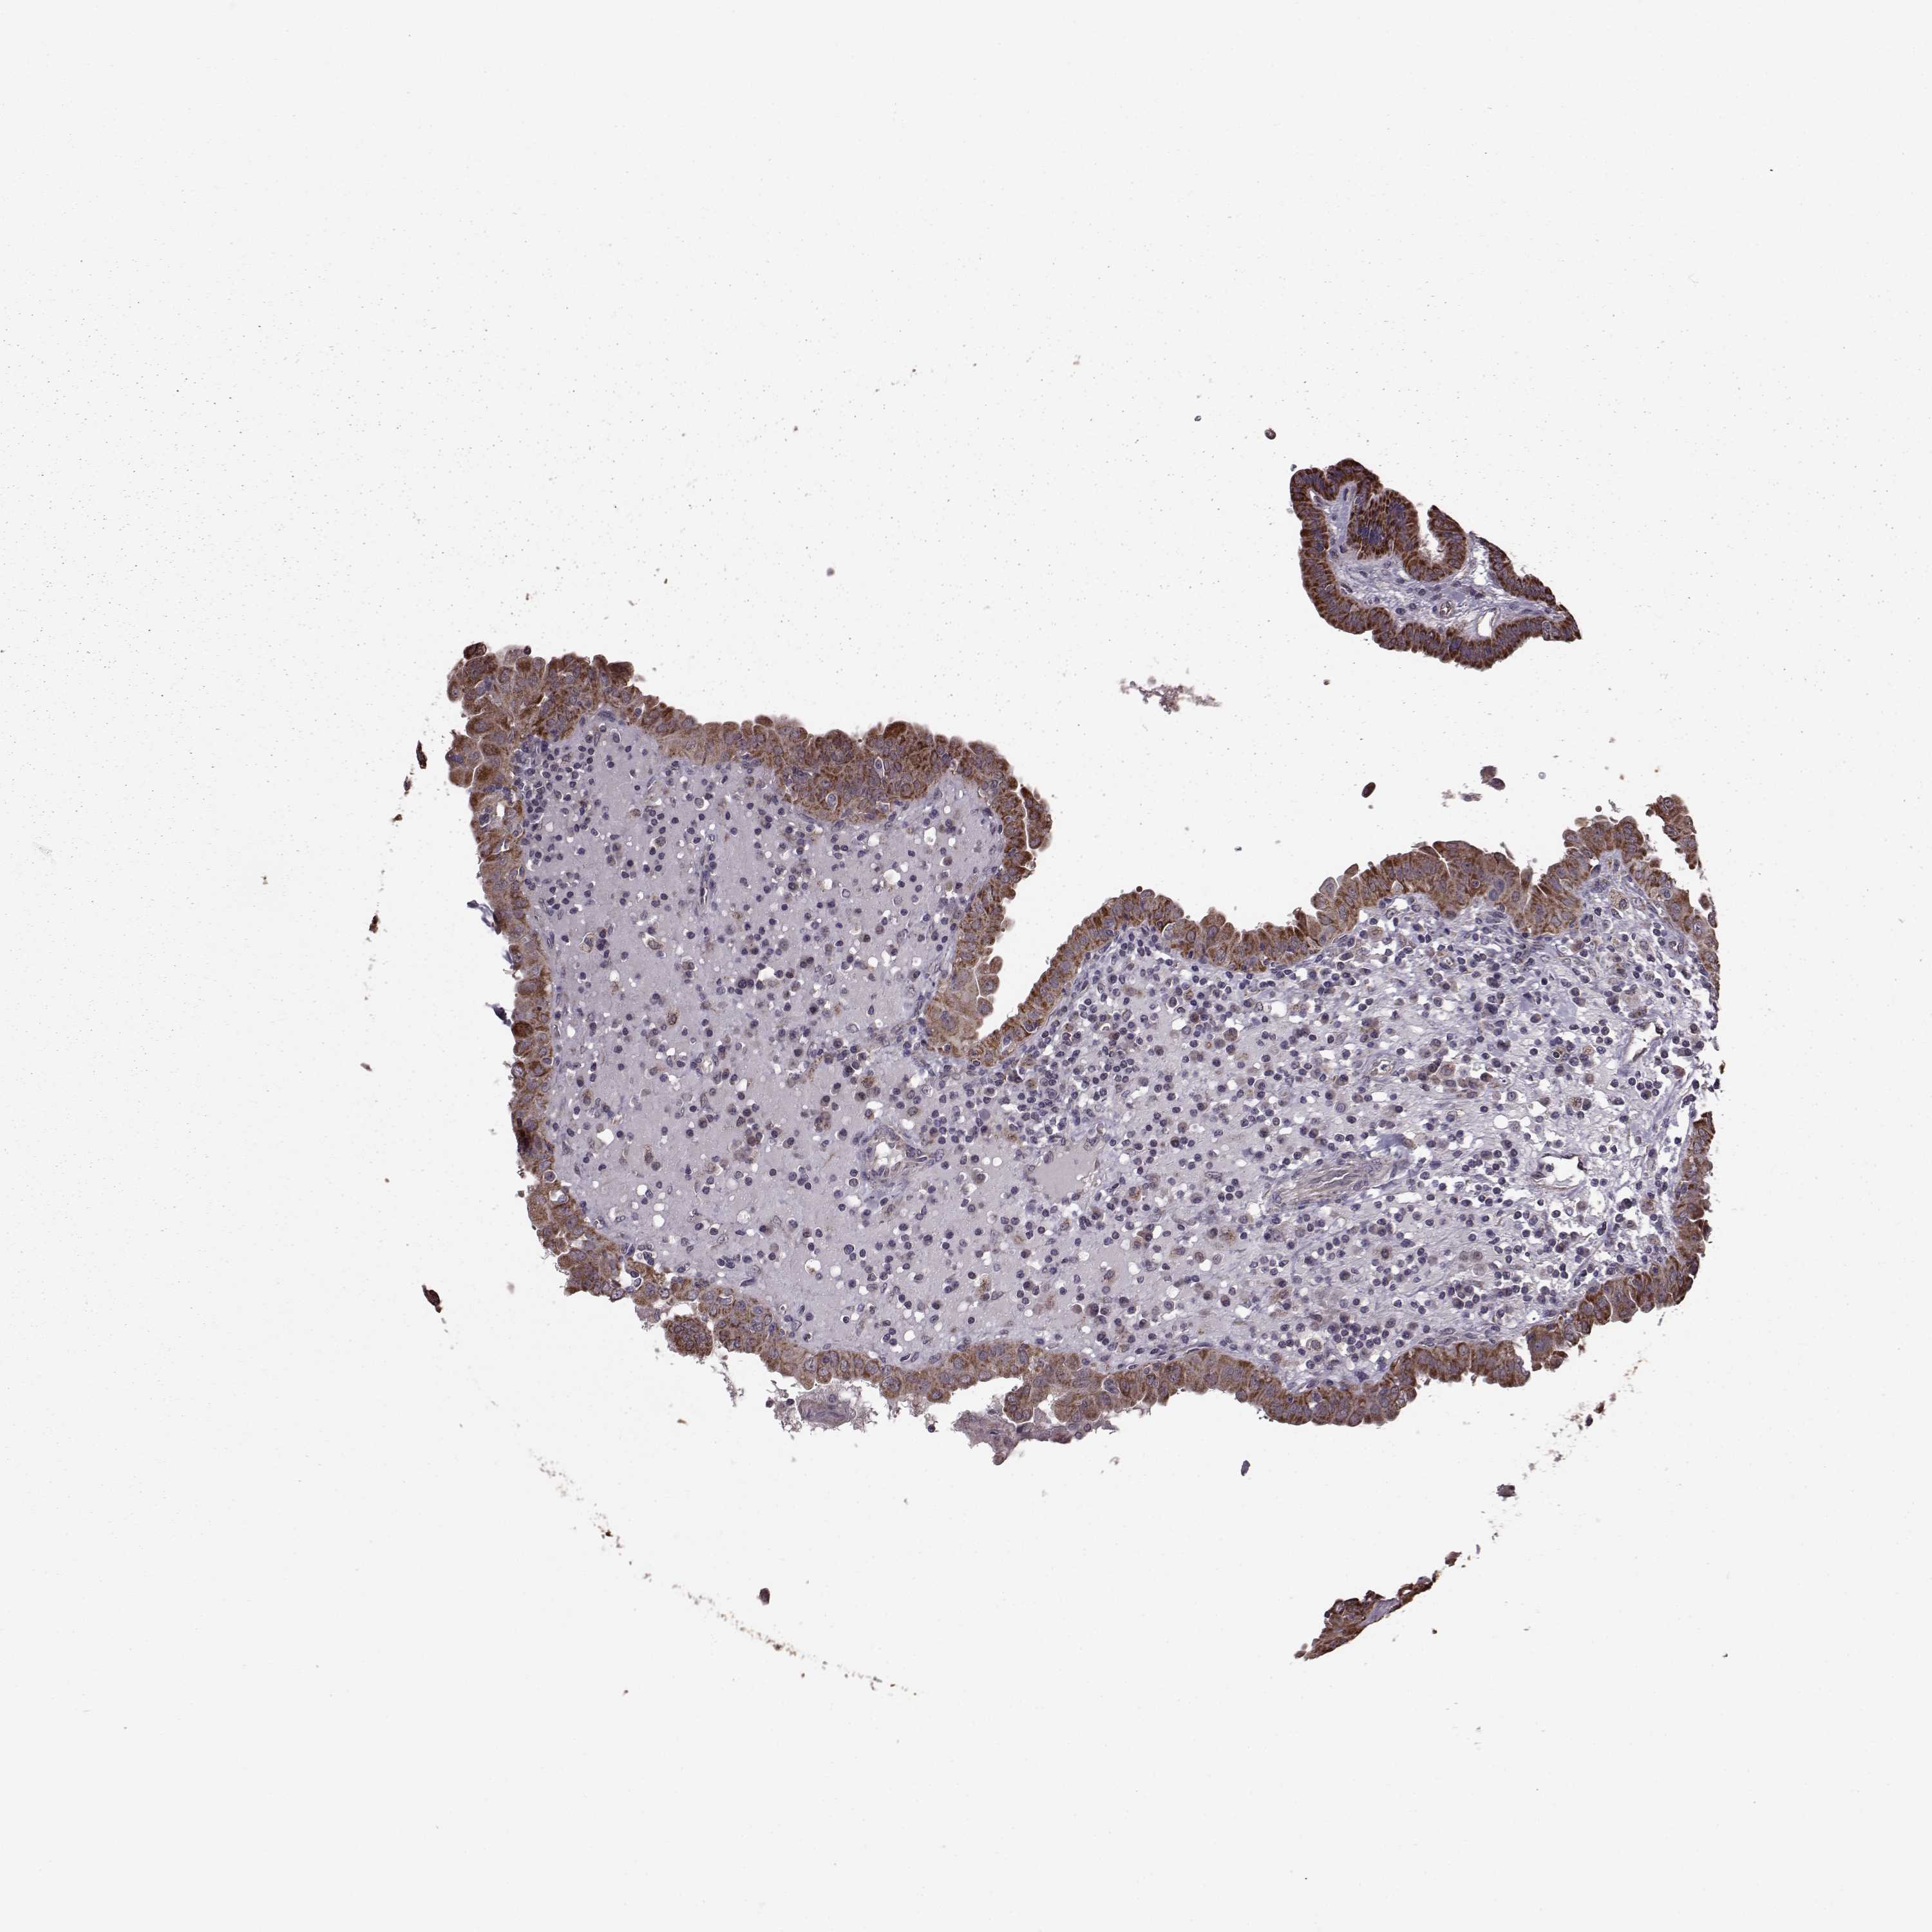

THYROID CANCER - Protein expressioni

A mouse-over function shows sample information and annotation data. Click on an image to view it in a full screen mode. Samples can be filtered based on level of antibody staining by selecting one or several of the following categories: high, medium, low and not detected. The assay and annotation is described here.

Note that samples used for immunohistochemistry by the Human Protein Atlas do not correspond to samples in the TCGA dataset.

Antibody stainingi

Antibody staining in the annotated cell types in the current human tissue is reported as not detected, low, medium, or high, based on conventional immunohistochemistry profiling in selected tissues. This score is based on the combination of the staining intensity and fraction of stained cells.

Each image is clickable and will lead to virtual microscopy that enables deeper exploration of all samples and also displays staining intensity scores, fraction scores and subcellular localization as well as patient and tissue information for each sample.

Antibody HPA072672

Staining

High

Medium

Low

Not detected

Intensity

Strong

Moderate

Weak

Negative

Quantity

>75%

75%-25%

<25%

None

Location

Nuclear

Cytoplasmic/membranous

Cytoplasmic/membranous,nuclear

Papillary adenocarcinoma, NOS

Follicular adenoma carcinoma, NOS